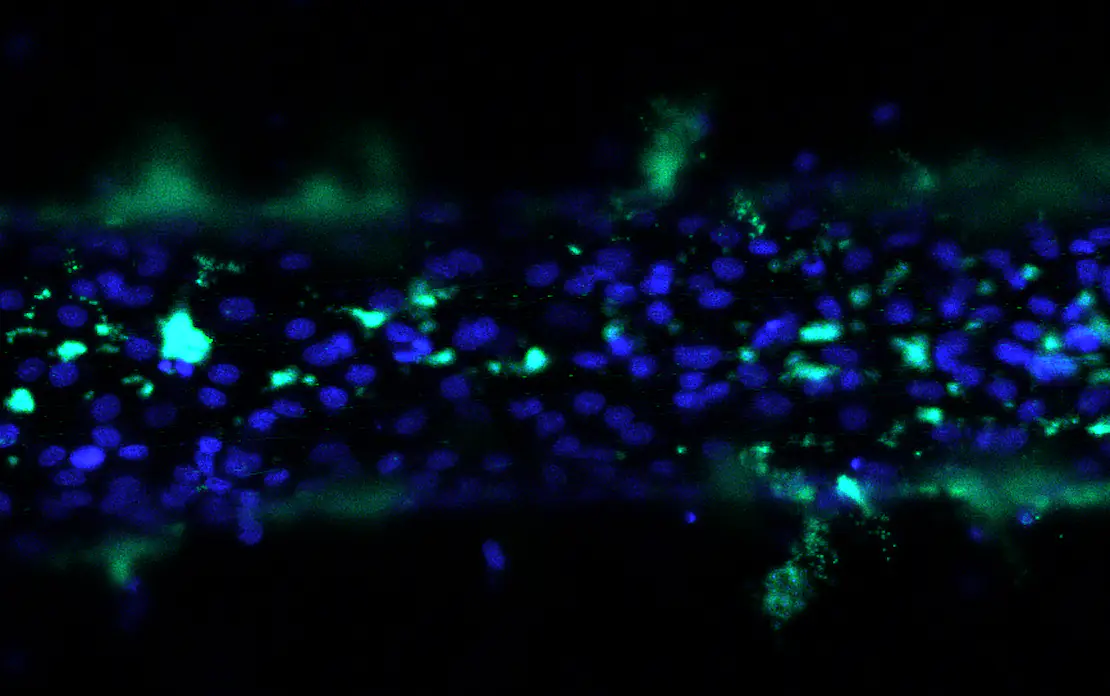

The researchers then pushed fluid through the channels and used fluorescent dye to track the resulting flow, capturing the process with a 3D confocal microscope. Their study showed the fluid particles could leak through the cell layer or get trapped in small pores.